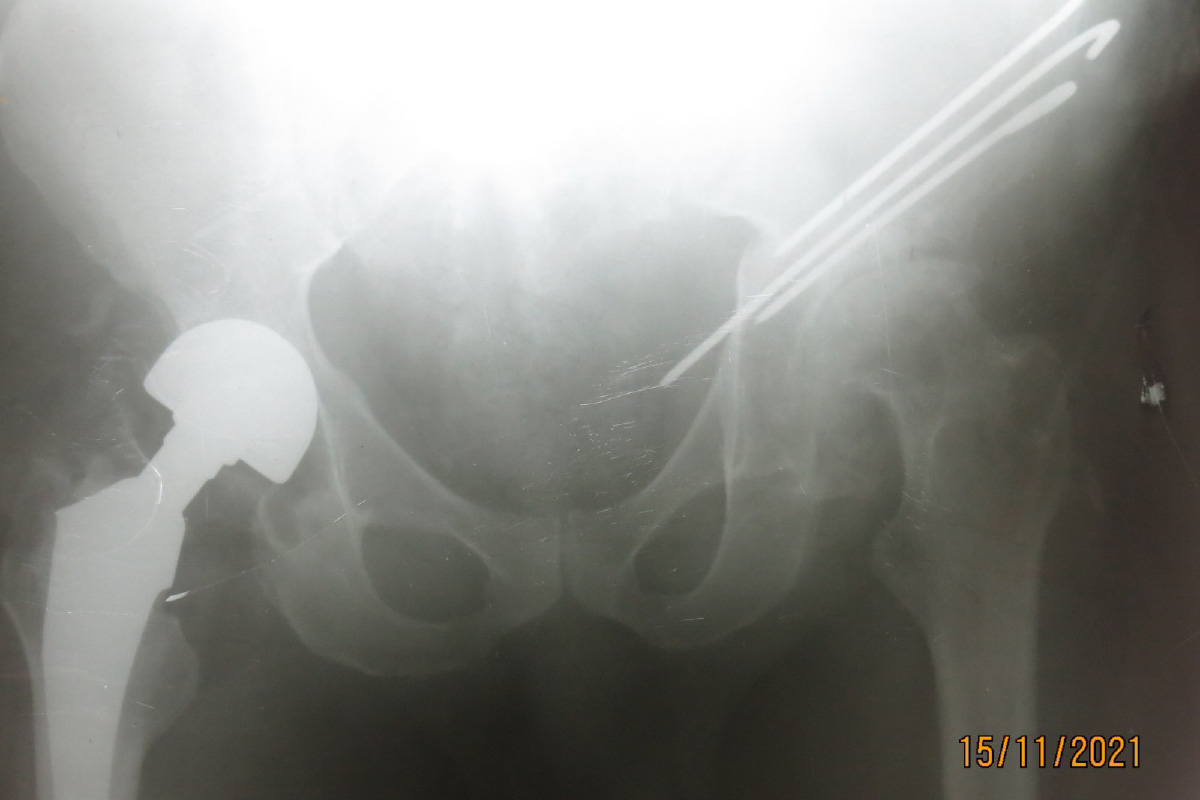

Wegen des fehlenden Screenings sind wir mit der kinderorthopädischen Krankheit Hüftdysplasie auch im Erwachsenenalter konfrontiert. Eine Option, für die eine Seite war hier die Chiari-Osteotomie, die genau für die Hüftdysplasie im Erwachsenenalter erfunden wurde. Für die andere Seite haben wir uns für ein künstliches Gelenk entschieden.

Daneben sind wir immer wieder mit komplexen Problemstellungen konfrontiert, wie hier mit diesem Jugendlichen, der eine Legg-Calvé-Perthes-Erkrankung durchlebt hat und diese Atrophie des betroffenen Beines und Adduktions-Kontraktur zeigt, wobei der entsprechende Beckenschiefstand rigide fixiert ist.